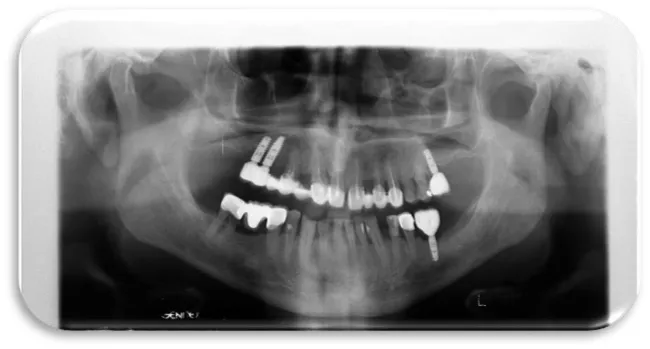

The seventh clinical case was male 33-year-old patient with good health condition and without any illness. He received dental implants in maxilla both in the right and the left posterior quadrant, 10 months ago. On the panoramic X-ray image marginal bone resorption changes were present in both jaws (maxilla and mandible). Bone resorption was observed on mesial and distal side from dental implants, also horizontal type of resorption is present (Figure 29).

The eighth clinical case is a female 42 year old patient, which is in good health and with good oral hygiene habits. Before a 9-months, she received two titanium dental implants. The position of the placed dental implants were in the mandible, in the posterior right quadrant. The dental implants were placed due to the missing of the second premolar and the first mandibular molar. A control X-ray image was made to the patient because of the suspicion that she has a peri-implant disease. In the clinical examination, it was found that the gingiva around the dental implants was swollen and hyperemic. The impressions and minimal bleeding were observed on the gingival palpation. The bleeding from the gingiva occur during the process of probing, and pocket depth of 3.5 mm was detected. After the performed x-ray examination, a very small marginal bone resorption was detected аnd no surgical intervention was required (Figures 30-32).